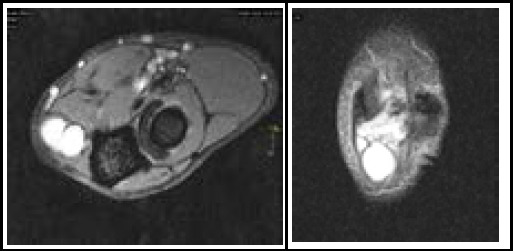

尺神经病变是一种常见的周围神经病变,肘管压迫是第二常见的上肢压迫综合征。神经节囊肿虽然罕见,但可导致肘管尺神经受压。在这里,我们提出了一个62岁的农民,长期患有糖尿病和血脂异常,他的内侧手指出现进行性疼痛和麻木,肘部屈曲加剧了这种情况。最初因汉森氏病被误诊并接受治疗。临床放射学评估显示左肘后内侧有多室囊性病变,压迫尺神经。手术切除神经节囊肿可减轻症状,但术后仍存在残余的运动缺陷。本病例强调了在肘管综合征鉴别诊断中考虑神经节囊肿的重要性,强调了在处理这种罕见病因时的诊断挑战和治疗考虑。

Ulnar neuropathy is a common peripheral neuropathy, with cubital tunnel compression being the second most frequent upper extremity compression syndrome. Ganglion cysts, though rare, can contribute to ulnar nerve compression in the cubital tunnel. Here, we present a case of a 62-year-old farmer with longstanding diabetes and dyslipidemia who experienced progressive pain and numbness in his medial fingers, exacerbated by elbow flexion. Initially misdiagnosed and treated for Hansen's disease. Clinico-radiological evaluation revealed a multiloculated cystic lesion in the posteromedial aspect of his left elbow, compressing the ulnar nerve. Surgical excision of the ganglion cyst alleviated symptoms, though residual motor deficits persisted postoperatively. This case underscores the importance of considering ganglion cysts in the differential diagnosis of cubital tunnel syndrome, highlighting the diagnostic challenges and therapeutic considerations in managing this rare etiology.